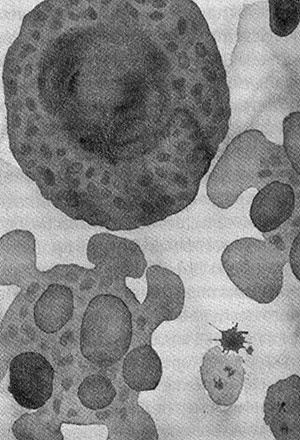

Когда клетки тела изнашиваются или повреждаются, они погибают в результате насильственного самоубийства — апоптоза. Клетка распадается на части, они упаковываются и перевариваются. Нарушение механизмов апоптоза приводит к раку — конфликту интересов отдельных клеток и организма в целом. Видимо, апоптоз необходим для обеспечения целостности многоклеточных организмов, но почему независимые клетки согласились на гибель ради высшего блага? Сегодня апоптоз контролируется митохондриями, которые унаследовали машину смерти от своих предков-бактерий. Так неужели целостность индивидуума действительно родилась в борьбе не на жизнь, а на смерть?

Смерть от апоптоза: жить клетке или погибнуть, решают митохондрии

«Я мыслю, следовательно, я существую», сказал Декарт. Так и хочется спросить: «Но что такое я?» Природа индивидуума, долгое время ускользавшая от философов и ученых, начала проясняться только недавно. Можно сказать, что индивидуум — это организм, состоящий из генетически идентичных клеток, которые специализированы для выполнения разных задач на благо организма в целом. С эволюционной точки зрения вопрос стоит так: почему эти клетки обуздали свои эгоистичные интересы и альтруистично сотрудничают в составе организма? Конфликты на разных уровнях организации — между генами, органеллами и клетками — неизбежны, но, как ни парадоксально, без этих междоусобных войн, возможно, никогда не возникли бы прочные связи клеток в пределах особи. Такие конфликты подхлестнули эволюцию молекулярной «полиции», которая обуздывает эгоистичные интересы примерно так, как правосудие обеспечивает приемлемое поведение членов общества. Центральным моментом полицейского контроля в организме является программируемая клеточная смерть — апоптоз. Апоптоз регулируется митохондриями, что наводит на мысль о том, что именно они сыграли ключевую роль в возникновении индивидуума. В этой части книги мы увидим, что в туманной глубине эволюционных времен митохондрии действительно были тесно связаны с возникновением многоклеточных особей.